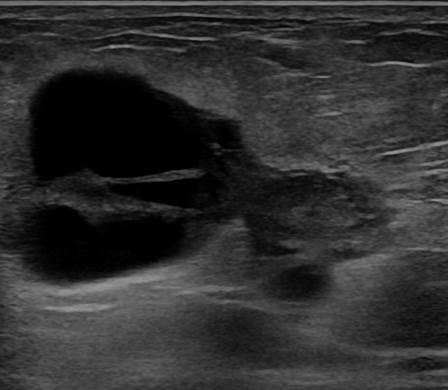

Ung thư vú

» Thông tin: Nữ giới – 55 tuổi.

» Lâm sàng: Khối tuyến vú.